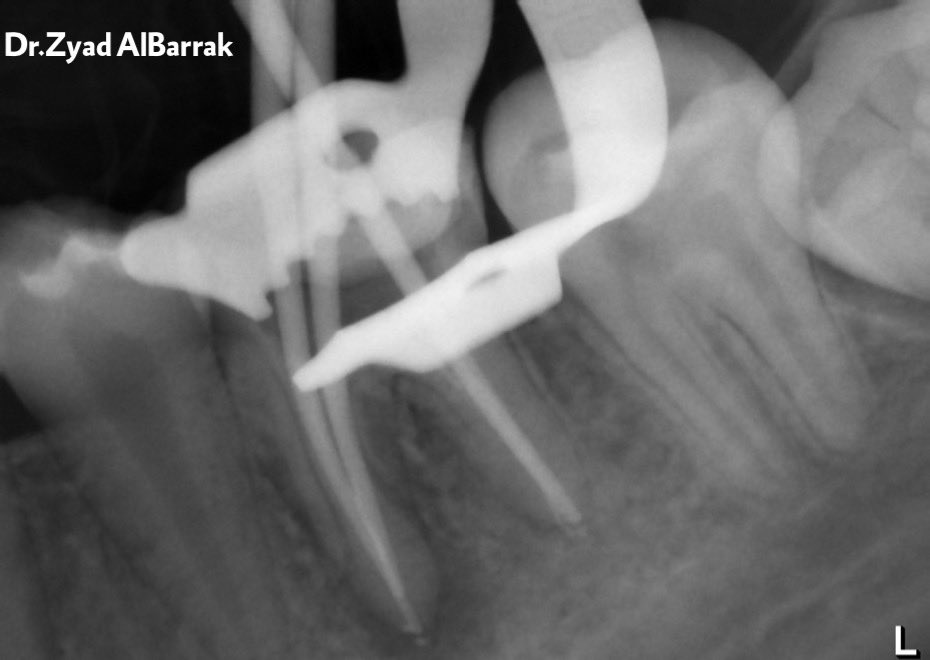

Remove all GP by profile ,(04- 30) file and chloroform to get access to all the canals.

Irrigate with NaOCL 5.25%, saline, CHX.